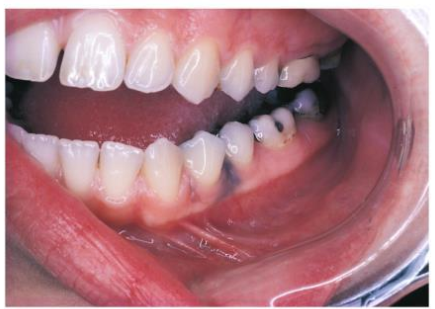

How are stainless steel and chrome crowns differentiated on a radiograph from amalgam or gold restorations?

SS crowns and chrome crowns have smooth and regular margins

usually used as a temporary restoration

Thin and do not absorb as much xrays → appear radiopaque but not as densely as amalgam or gold

may have some “see-through”ish areas on radiograph.